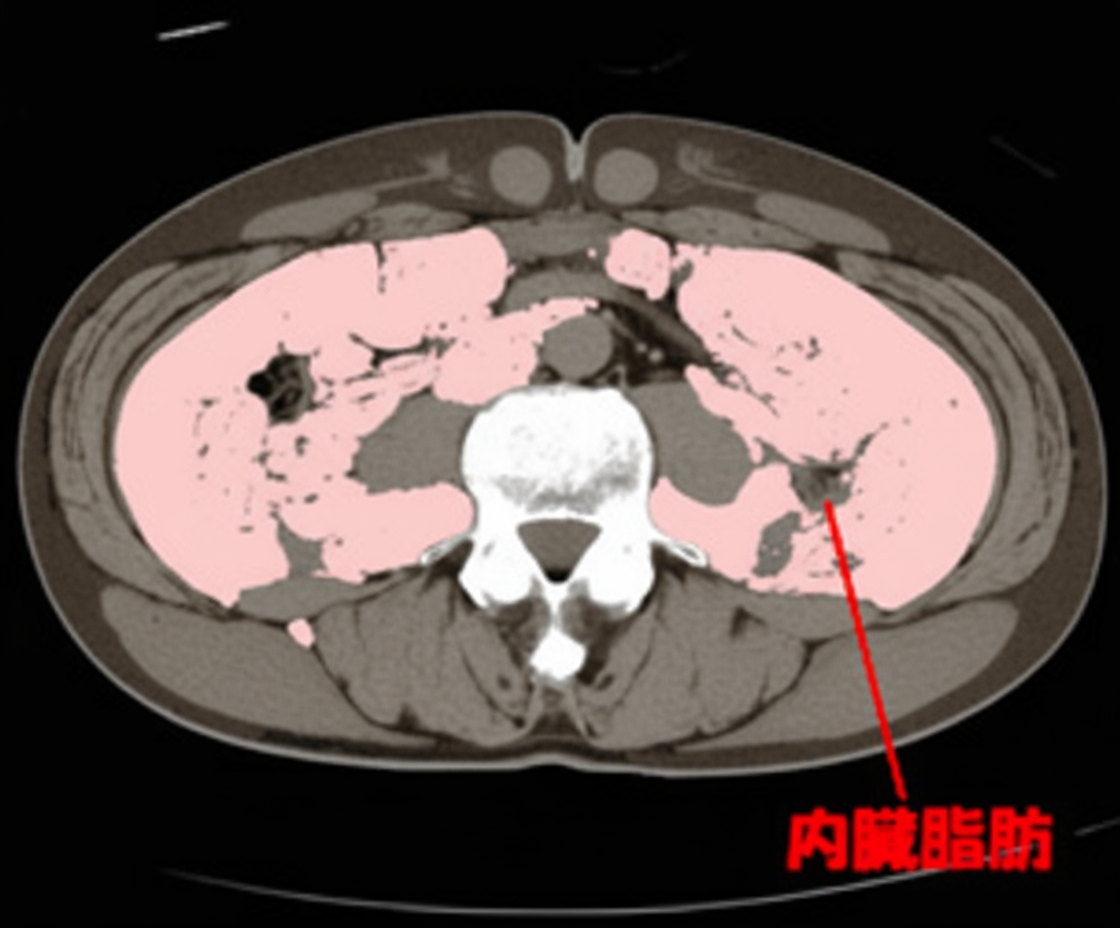

内臓脂肪計測(40歳以上の方)

内臓脂肪≧100㎠は危険!

平成20年春から特定検診(=通称メタボ検診)が始まりました。

腹囲が男性85cm、女性 90cmを超えた方は「内臓脂肪蓄積」として要注意と判定されます。

でも、上の図からも判るように腹囲は必ずしも内臓脂肪量を反映しないのです。 自分のお腹の中身を知って、今後の健康管理に役立てましょう!

脂肪には「内臓脂肪」と「皮下脂肪」があります。「内臓脂肪」は、過剰に蓄積すると動脈硬化を進めて脳卒中や心筋梗塞を起こす原因になります。(皮下脂肪優位型の方の動脈硬化リスクは高くありません。)

内臓脂肪の蓄積により「高血圧」「高脂血症」「糖尿病」などの生活習慣病が引き起こされた状態を「メタボリックシンドローム(代謝異常症候群)」と呼び、脳梗塞や心筋梗塞を発症するリスクが約5倍高くなります。

日本肥満学会では、へその位置の内臓脂肪面積が100c㎡を超えた場合を病気としての「肥満症」と判定しています。検査はCTによるへそ断面の撮影で3分ほどで終了します。この機会に一度、自分の動脈硬化リスクを見つめ直してみませんか。

なお、 この検査は、へそをねらってごく少ない照射量で撮影するので、普通のCT撮影に比べてはるかに安全ですが、念のため対象者は40歳以上の方とさせていただきます。 腹部CTをお受けになる際一緒に測定するのが、特にお勧めです。